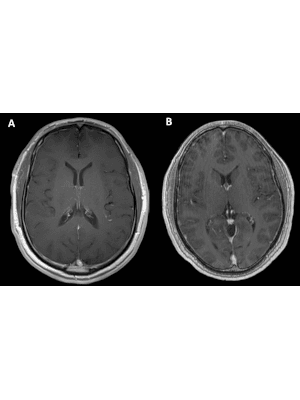

Meningeal abnormalities

The aim of this article is to provide a structured approach for detecting and interpreting common pathologies involving the meninges. It is important to understand meningeal anatomy, the relationship of the meninges to the blood-brain barrier (BBB), and the effect of the MRI protocol on the normal enhancement characteristics of the meninges to accurately diagnose meningeal abnormalities.